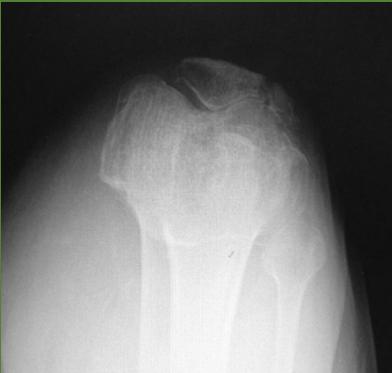

| Entry Points | Proximal Tibial Site: - Insertion: Laterally at a point 2cm distal and 2cm posterior (lateral) to the Tibial tuberosity. - Exit: Medially. - Avoids: Injury to the common peroneal nerve. Distal Femoral Site: - Insertion: Medially at level of upper patella in-line with mid-femur. - Exit: Laterally. - Avoids: Popliteal vascular damage and intra-articular injury. | Proximal Tibial Site: Distal Femoral Site: ![]() |